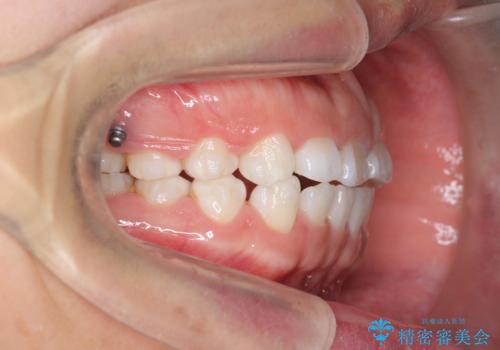

インビザライン 気になるすきっ歯の改善

- 上下顎前歯部の空隙が気になるので治したいと当院にいらっしゃった方の症例です。

非抜歯、インビザラインによる矯正治療により歯と歯の隙間および前歯の上下の隙間を閉じ切りました。